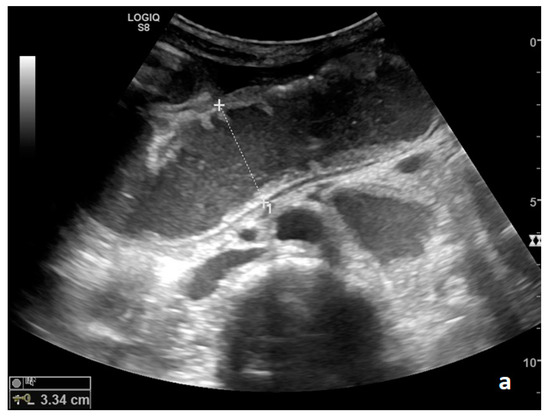

Figure 2.

A dilated small bowel loop with a caliber of more than 3 cm (dotted line) with trapped feces defines a ‘small bowel feces sign’. Bowel walls appear thin, and the folds flatten.

The valvulae conniventes (Kerckring valves, circular folds) are permanent folds composed of mucosa and submucosa that project into the intestinal lumen and are clearly visible in the case of fluid distension (keyboard sign) [31]. At an early stage of SBO, it is not uncommon to see the valvulae in the upstream loop appearing more numerous and closer to each other. As the occlusive state continues, the loop upstream of the obstructive fulcrum becomes weaker, bowel walls appear thin, and the folds flatten (Figure 2a and Figure 3a,b). The upstream loops more distant from the obstructive fulcrum may still present peristalsis, albeit reduced and ineffective. In complicated ileus, with the onset of vascular loop distress, the walls and valvulae become thicker and weaker due to parietal edema and venous stasis, with possible dramatic parietal necrosis and subsequent perforation (Figure 4a–d and Figure 5a,b) [12,43].